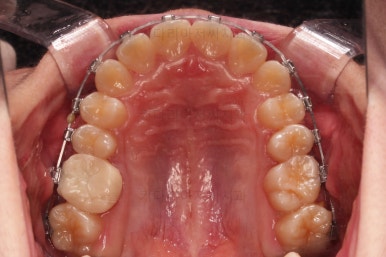

연산동치과 초진 시, 입안의 모습입니다.

보시다시피 앞니쪽이 많이 삐뚤고요. 어금니쪽이 긴밀하지 못한 부정교합이 있네요.

그리고 왼쪽 하단의 사진에 화살표를 보시면, 예전에 신경치료를 해둔 치아인데 어린 나이에 신경치료를 하다보니 크라운으로 치료를 마무리 하지 못했어요.